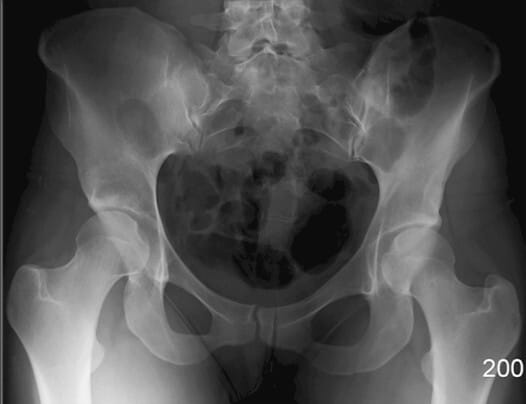

폐쇄공 (Obturator Foramen)

| 폐쇄공 (Obturator Foramen) |

| ✅ 치골과 좌골 사이에 위치한 크고 타원형의 개구부로, AP view에서는 골반 하단 양측에 대칭적인 투과성 음영으로 보입니다. |

| 🔴 골반 골절에서 비대칭이나 모양 변화가 나타날 수 있는 부위입니다. |